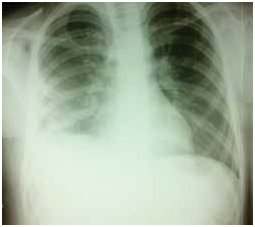

After discharge, all patients were treated with X-ray after 6 months of primary therapy. The criteria for radiological improvement were the loss of shaded cysts, and the resorption of postoperative pericystic inflammation and pleural reaction (Figure 12­–15).

Figure 12 Preoperative x-ray, right round shadow.

Figure 13 Postoperative x-ray, pericystic cavity non-capitonnage method.

Of the 80 patients treated in this study, we did not have a single case of relapse. Considering the large number of complicated, gigantic and multiple cleaners in both groups, we consider this result satisfactory. The literature published a recurrence rate of 2-12% while Sayir and associates had a recurrence rate of 1.4%.36 We further analyzed the finding of a control chest X-ray of the lung image 6 months after surgery. The success of the procedure was characterized by radiological improvement after 6 months. Radiological improvement was characterized by absence of atelectasis, loss of shadow operated cysts and resorption of postoperative cystic inflammation.

Based on the analyzed data of radiological recording in the investigated group, no subjects with lung atelectasis were recorded after surgery, while in the control group this complication occurred in 7 subjects. In the examined group, there was a disappearance of shadow of operable cyst in 31 subjects, while in the control group there were 20 respondents with shadow disappearing after 6 months. In the investigated group, there was a resorption of postoperative inflammation in 37 subjects, while in the control group there were 27 subjects who recorded resorption of postoperative pericystic inflammation. Following three radiological parameters, 6 months after surgery: the presence of atelectasis, the disappearance of shadow-operated cysts, and the resorption of postoperative periclinic inflammation, we concluded that the regression of radiological changes was significantly more pronounced in the test (capitonnage) compared to the control group (non-capitonnage).